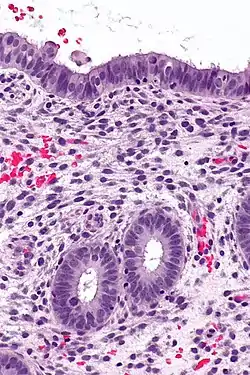

(A) proliferative endometrium (Left: HE × 400) and proliferative endometrial cells (Right: HE × 100)

(B) secretory endometrium (Left: HE × 10) and secretory endometrial cells (Right: HE × 10)

(C) atrophic endometrium (Left: HE × 10) and atrophic endometrial cells (Right: HE × 10)

(D) mixed endometrium (Left: HE × 10) and mixed endometrial cells (Right: HE × 10)

(E): endometrial atypical hyperplasia (Left: HE × 10) and endometrial atypical cells (Right: HE × 200)

(F) endometrial carcinoma (Left: HE × 400) and endometrial cancer cells (Right: HE × 400).